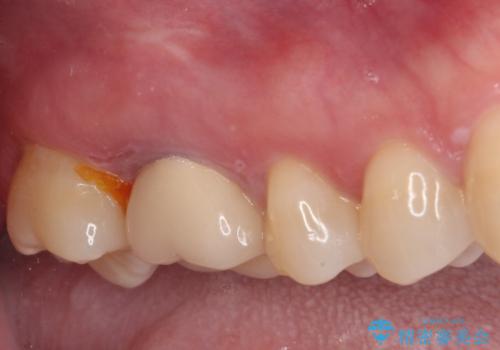

- 上下の奥歯に違和感を感じ、近医にて虫歯を指摘されたとのことで来院された患者様です。

診査したところ、下顎の奥歯は膿の出口ができており、上顎の奥歯は噛んだときに痛みを感じている状態でした。

まずは根管治療を行い、症状が落ち着いたことを確認して、オールセラミッククラウンにて補綴治療を行うこととしました。

処置後、下顎の膿の出口はすぐに消えましたが、レントゲン写真からも分かるとおり、歯根途中に穴が開いており、充填材が歯根外にはみ出していました。数ヶ月経過を見たところ、特に異常は認められなかったため、補綴治療を行いました。